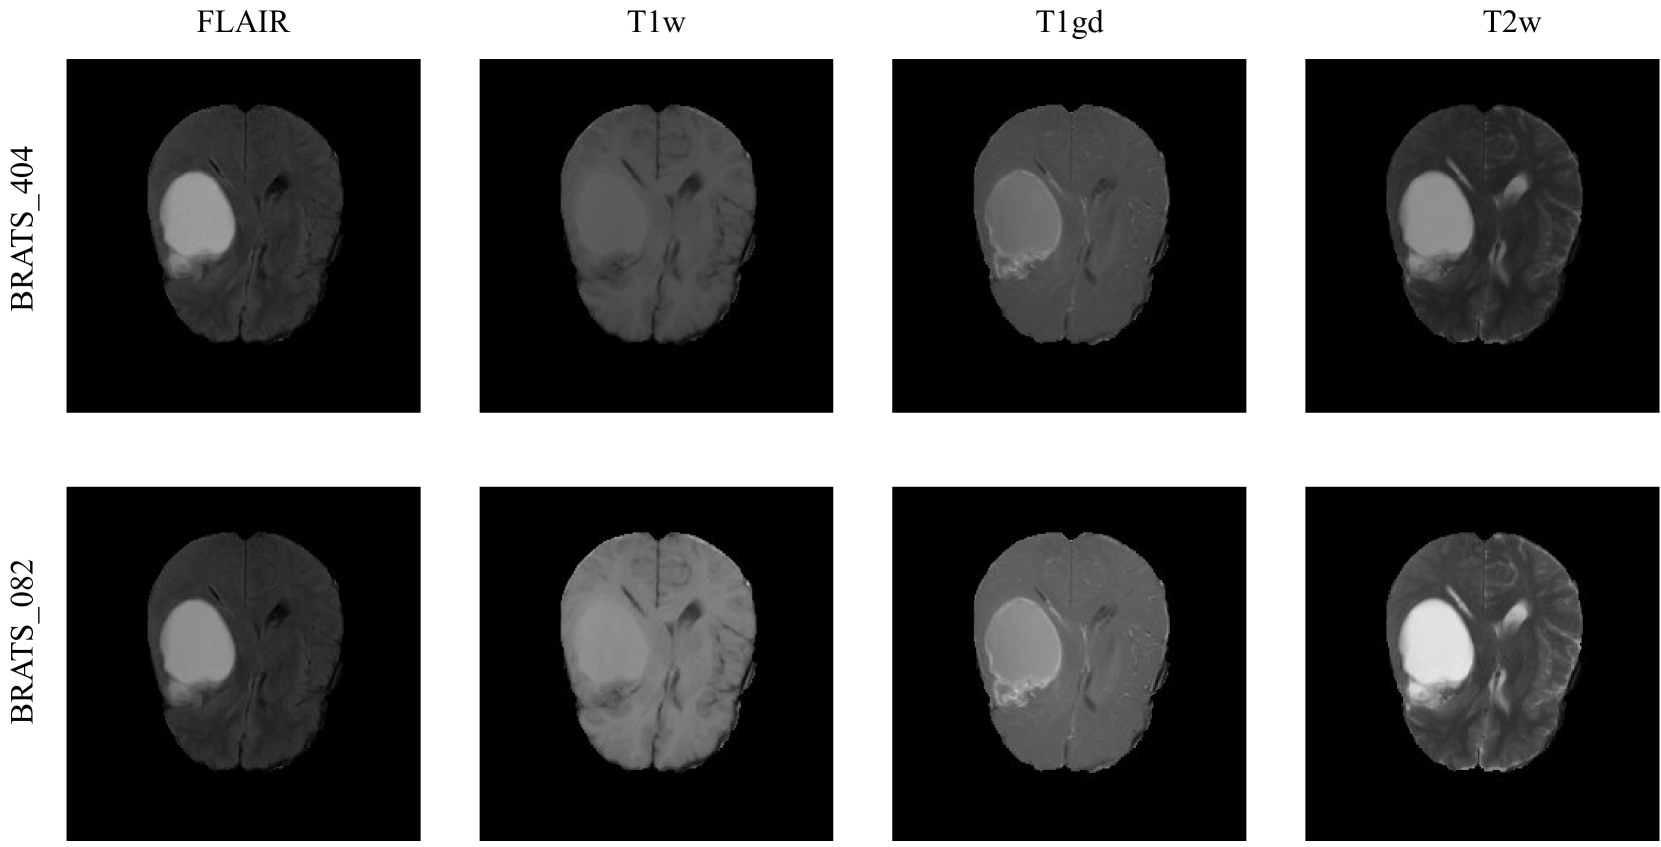

In Table V, we present the best sensitivity and specificity results for (near-) duplicate detection on buckets 2A, 2B, 2C using the top-3 retrievals obtained through DINOv1 embeddings with HNSW indexing. Overall, for stage 1, the mean sensitivity score is 0.9645, while for stage 2, it is 0.9407. In terms of mean specificity, we found scores of 0.8559 for stage 1 and 0.8373 for stage 2. Rotation exhibits the lowest sensitivity, mirroring trends observed in the training dataset. We also observed some false positive occurrences that are indeed in our database, which is due to the fact that possible identical images are shared among different MSD tasks. Upon scanning through 10 tasks, we were able to find 28 pairs of possible (near-) duplicates in the original MSD dataset shown in Table B.1. The majority of detected (near-) duplicates are from task 1, which contains the MRI brain images. An example is shown in Figure B.1 where two cases are different only in the brightness.

Refer to caption

Figure B.1: Example of a near-duplicate found in MSD dataset. The BRATS_404 and BRATS_082 are a near-duplicate pair that is different only in the brightness.